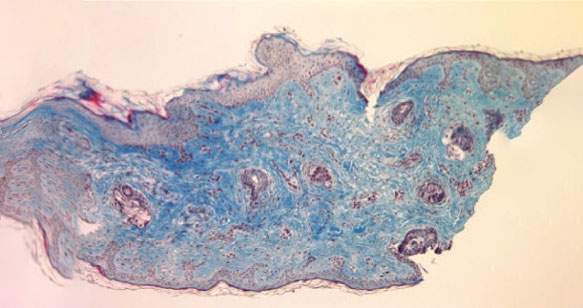

Aumento visibile della quantità di collagene (in blu) in 12 settimane di trattamento.

Biopsia prima del trattamento

12 settimane dopo il trattamento

Gli studi effettuati mostrano che Kleresca® Skin Rejuvenation induce un aumento di circa il 400% della produzione di collagene.